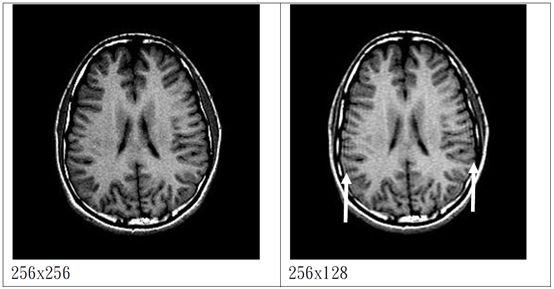

截斷假影(Truncation artifact):

又稱 Gibbs artifact

主要發生在高對比度的界面(ex:頭骨/腦、脊索/CSF),會造成交替的明暗帶(ex:脊髓之假性廔管)

原因是由於樣品數或取樣時間的限制,訊號的強度不可能成階梯狀變化,容易發生在相位編碼(phase encoding)方向。

u 解決方法:

² 增加matrix size

² 增加取樣時間

² 減少像素大小(增加相位編碼的數目、減少FOV)